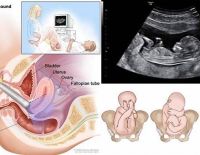

Tác dụng của siêu âm đầu dò âm đạo và những điều cần biết

Siêu âm đầu dò âm đạo là kỹ thuật giúp kiểm tra và nhận định chính xác tình trạng sức khỏe sinh sản của nữ giới. Đồng thời có thể nhận biết được việc mang thai ngoài tử cung, các khối u bên trong. Vậy...